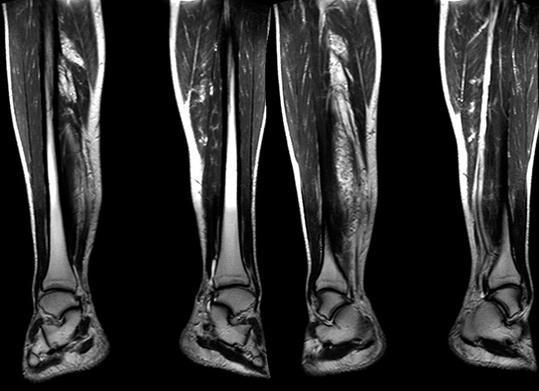

МРТ нижних конечностей — назначение, проведение, противопоказания

С каждым годом врачи дают направление на МРТ (магнитно-резонансную томографию) всё чаще. Это связно с высокой информативностью метода, его неинвазивностью и безболезненностью проведения. Этим методом можно детально изучить каждый орган человеческого тела, сосуды, вены и артерии, а также все ткани, из которых состоит тело.